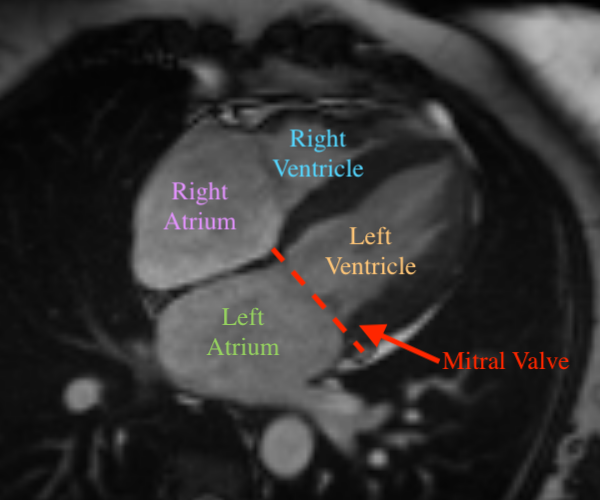

Mitral regurgitation (MR) [7] is a valvular heart disease in which the mitral valve does not close completely during systole when the left ventricle contracts, causing regurgitation – leaking of blood backwards – from the left ventricle (LV), through the mitral valve, into the left atrium (LA) – Figure 1. MR can be caused by either organic or functional mechanisms [6], with organic MR leading to atrial and annular enlargement and functional MR increasing atrial pressure. As MR progresses, it may cause arrhythmia, shortness of breath, heart palpitations and pulmonary hypertension [14]. Left undiagnosed and untreated, MR may cause significant hemodynamic instability and congestive heart failure which can lead to death [17], while acute MR usually necessitates immediate medical intervention [22]. Thus, early detection and assessment of MR are crucial for optimal treatment outcomes, with the best short-term and long-term results obtained in asymptomatic patients operated on in advanced repair centers with low operative mortality (<1%absentpercent1<1\%) and high repair rates (8090%absent80percent90\geq 80-90\%[7].

Figure 1: Three cardiovascular magnetic resonance (CMR) images showing the long-axis four-chamber view of the heart. Left: a heart with normal mitral valve. Middle: a heart with normal mitral valve when the valve leaflets are open. Right: a heart with mitral regurgitation. The red dotted line denotes the mitral valve.